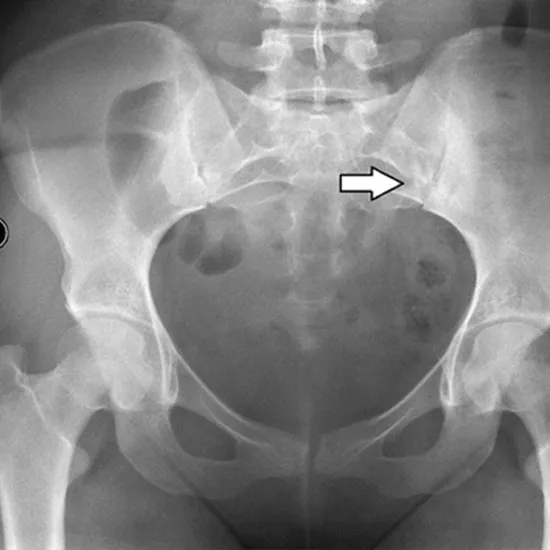

X-Ray Each of the Sacro-Iliac Joints AP View is utilized to visualize the back region where the spine and pelvis meet (hip bones).

The doctor prescribes this test to identify and diagnose the reason for lower back pain, which could be sacroiliitis (inflammation of this joint) or ankylosing spondylitis (a form of arthritis that affects the spine). In addition to detecting aberrant development or fracture of the bones in this region, the test can also monitor the bone's healing after it has been set.